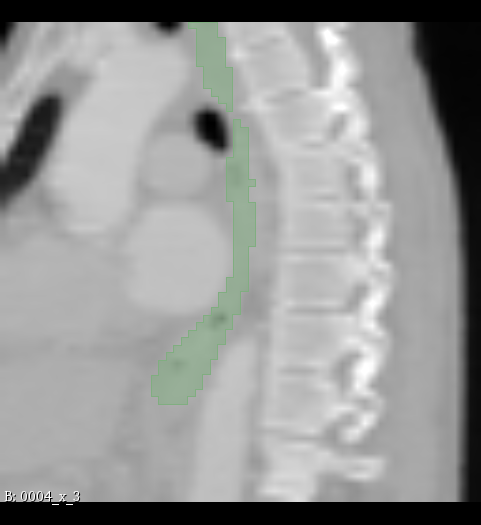

Figure 2: Illustration of the data from the TotalSegmentor data set [32] used in the experiments. The first row shows the axial, coronal and sagittal views passing the center of mass of the kidney in one of the data points. The second row shows the axial, coronal and sagittal views passing the center of mass of the aorta in one of the data points. The third row shows the axial, coronal and sagittal views passing the center of mass of the esophagus in one of the data points.

The experiments are conducted with respect to the TotalSegmentor data set [32]. This data set contains 1204 CT images with 104 anatomical structures (27 organs, 59 bones, 10 muscles, 8 vessels). To illustrate the effect noise may have on organs with different shape, three different organs are chosen. This includes the right kidney which in general is pretty spherical, the aorta which is tubular and relatively thick and the esophagus which is tubular and relatively thin. For each of the organs, 400 cases is selected and split into 5 folds of 80 cases. Finally, the images are sub-sample to half resolution and patches of 643superscript64364^{3} voxels centered in each of the structures are extracted.